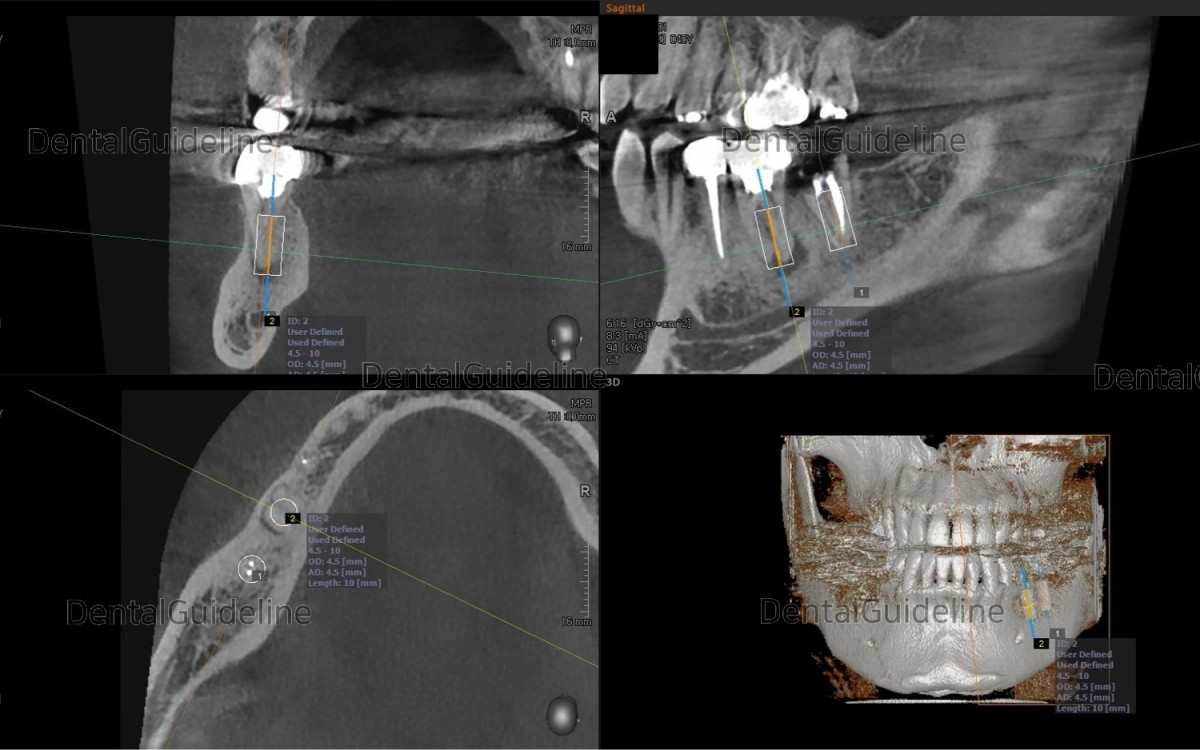

Rough simulation on the CBCT scan views The socket size of the 1st molar didn’t seem to accept the immediate placement of an implant It seems hard to get initial stability.